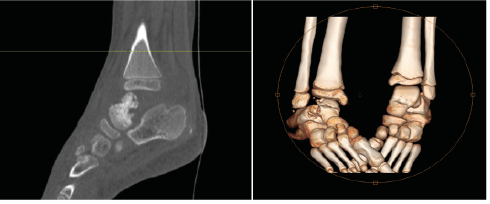

Child Ismail A., 7 years old, without Special pathological history presenting to the pediatric emergency room for a red, swollen, and painful right ankle (Figure 1), related to septic arthritis secondary to a neglected wound. On clinical examination: febrile at 39 °, asthenic, BP 110/70 mmHg, heart rate 130 bpm, and oxygen saturation 98%. Cardiovascular and pleuropulmonary auscultation were normal.

Figure 1: The Red and Swollen Ankle